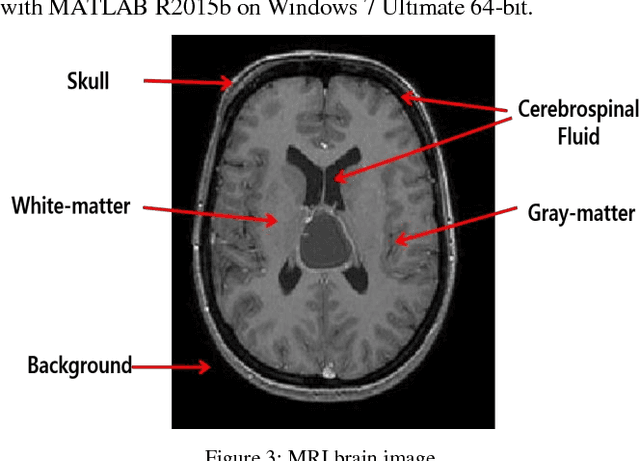

Abstract:Medical image segmentation being a substantial component of image processing plays a significant role to analyze gross anatomy, to locate an infirmity and to plan the surgical procedures. Segmentation of brain Magnetic Resonance Imaging (MRI) is of considerable importance for the accurate diagnosis. However, precise and accurate segmentation of brain MRI is a challenging task. Here, we present an efficient framework for segmentation of brain MR images. For this purpose, Gabor transform method is used to compute features of brain MRI. Then, these features are classified by using four different classifiers i.e., Incremental Supervised Neural Network (ISNN), K-Nearest Neighbor (KNN), Probabilistic Neural Network (PNN), and Support Vector Machine (SVM). Performance of these classifiers is investigated over different images of brain MRI and the variation in the performance of these classifiers is observed for different brain tissues. Thus, we proposed a rule-based hybrid approach to segment brain MRI. Experimental results show that the performance of these classifiers varies over each tissue MRI and the proposed rule-based hybrid approach exhibits better segmentation of brain MRI tissues.